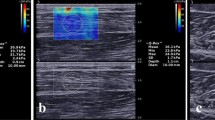

Representative SWE images at each time point between the experimental leg and the control leg are illustrated in Fig. 4.

Measurement of shear elastic modulus and echogenicity

The circular regions of interest (ROIs) were set in the color-coded box presentation (2 cm × 2 cm) in the SWE mode. Three random circular ROIs with a diameter of 5 mm were set in the color-coded box (Fig. 9). Random circular ROIs were picked immediately after each ultrasound image was acquired. Then, the shear elastic modulus at the set ROI was automatically calculated using the ultrasound imaging machine. A minimum of 15 circular ROIs was obtained. The mean shear elastic modulus values of the three circular ROIs were calculated for statistical analysis.